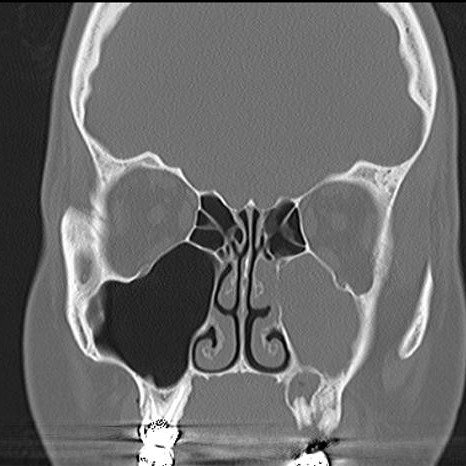

Gali būti atliekama ir kompiuterinė tomografija (KT) – tai yra auksinis standartas diagnozuojant OŽS (4 pav.) (2). KT vertinamas periapikalinio pūlinio santykis su ančio dugnu, tiksli svetimkūnio vieta, žandinio ančio kaulinė erozija, oroantralinė fistulė (2, 3). Kaip ir panoraminėse radiogramose, gali būti randama plombinės medžiagos ar lūžusių endodontinių instrumentų antyje (3). Radiologiniuose vaizduose stebimas gleivinės paburkimas, kuris gali būti lokalus, matoma vadinamoji skysčio linija dėl pūlingo uždegimo. Žandiniam ančiui esant visiškai pripildytam pūlingo eksudato, KT vaizduose stebimas ančio oringumo sumažėjimas ir vadinamasis ro radiologinis vaizdas.

4 pav. Kairiojo žandinio ančio sinusito KT (12)